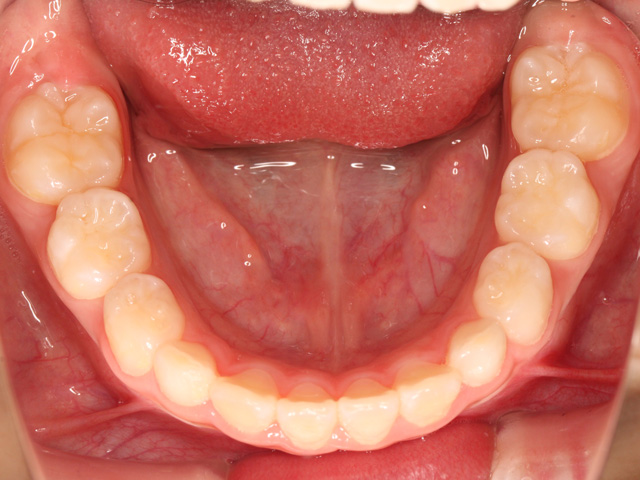

永久歯がすべて生え揃ってから行う大人の矯正とは異なり、顎の成長をコントロールしながら、歯が正しく並ぶための土台を整えていくのが特徴です。

身体全体が「一次成長」と呼ばれる骨格的成長が旺盛な段階なので、それに乗じて顎の骨も成長します。成長段階にある骨は成長が完了した成人と比較すると柔らかく、例えるならまだ固まっていない粘土のような状態です。

そのため、小児矯正では歯列不正(歯並びが悪い状態)を効率良く歯を動かすことが可能で、装置の選択が適切であれば、短い期間で歯並びを改善させることができます。

乳歯と永久歯が混在している段階を「混合歯列期(こんごうしれつき)」と専門的にに呼びますが、この段階で歯列不正があった場合に、顎の成長を活かしつつ歯並びの改善を同時に行う治療をこのように呼びます。